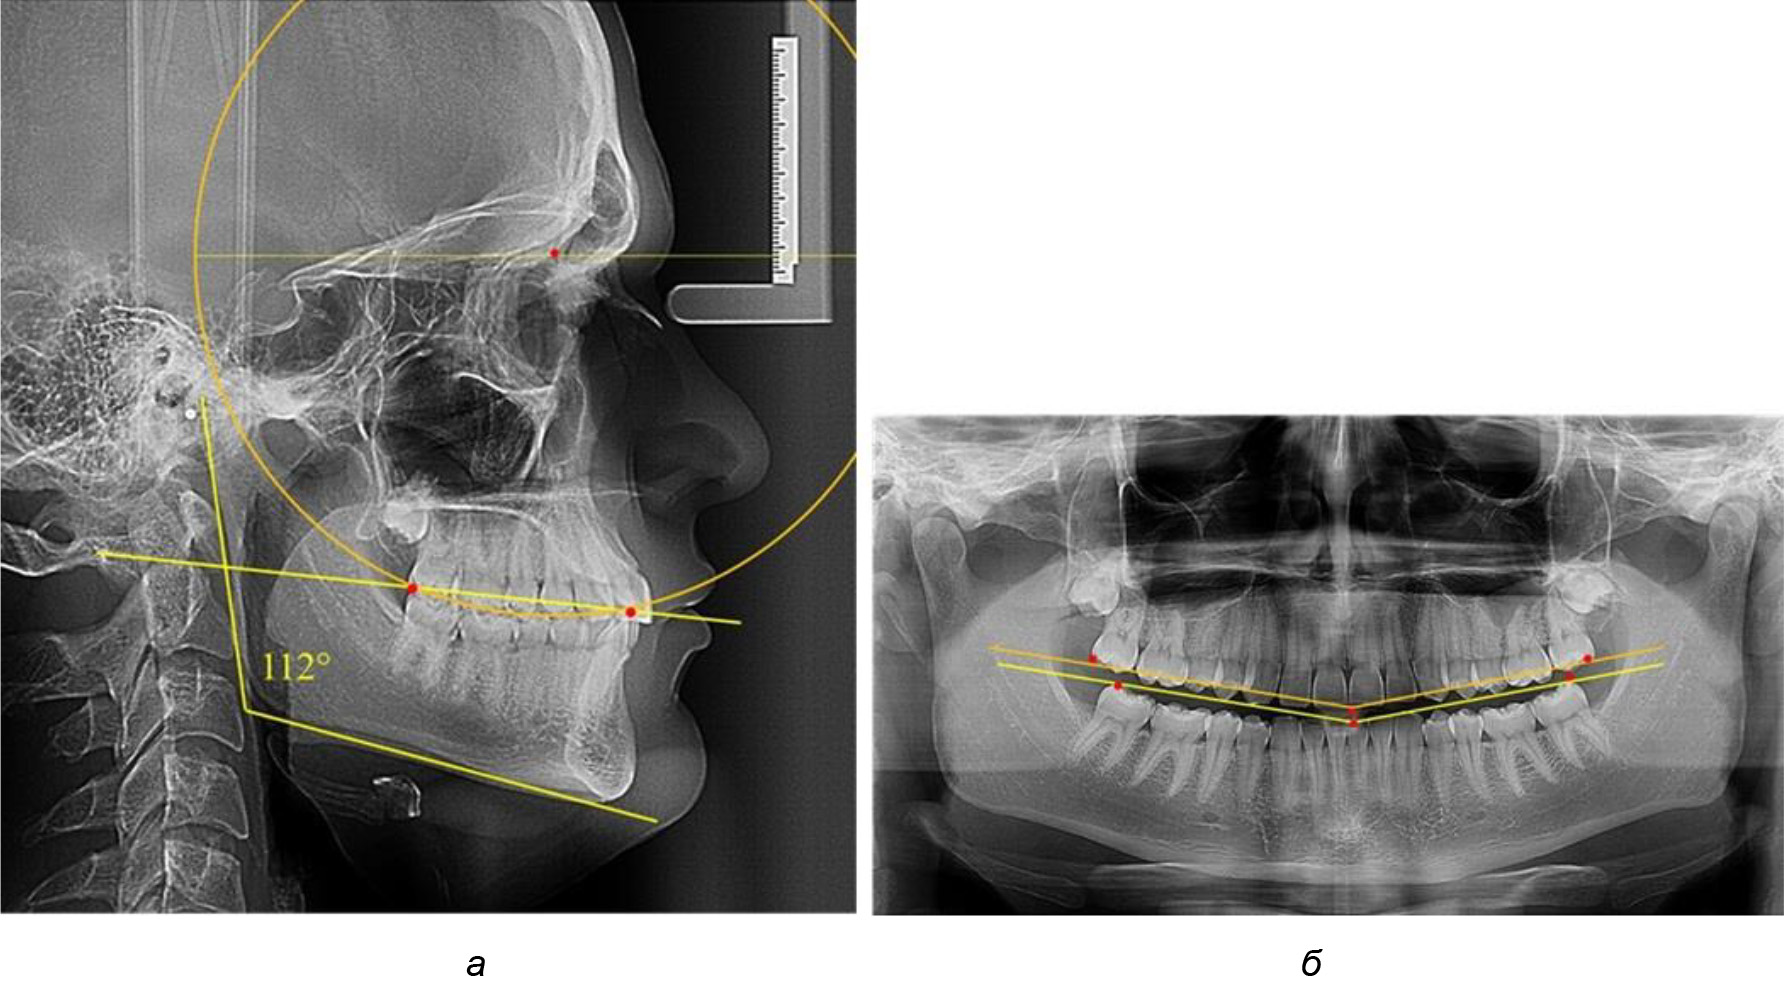

В ходе исследования установлено, что в 1-й подгруппу вошли ТРГ и ОПТГ 18 человек 1-й группы, что составило (29,03 ± 5,78) % от всех пациентов, рентгенограммы которых были проанализированы. У всех пациентов величина угла нижней челюсти была более 125° и в среднем составила (129,89 ± 3,62)° и характеризовала вертикальный тип нижней челюсти.

Учитывая существенную вариабельность линейных показателей, обусловленных типологическими (гнатическими и дентальными) вариантами зубочелюстных дуг, анализ проводили только при измерении глубины кривой Spee в наиболее углубленном месте и оценивали относительный показатель через отношение радиуса круга к сагиттальному расстоянию окклюзионной линии.

Анализ результатов показал, что глубина кривой Spee в среднем по подгруппе составил (4,12 ± 0,53) мм как при анализе ТРГ, так и ОПТГ.

Деление величины радиуса круга к длине окклюзионной линии составило 1,623 ± 0,02. Таким образом, для определения радиуса окружности, соответствующей кривизне окклюзионного контура боковой ТРГ, необходимо измерить расстояние между передней и задней окклюзионными точками и последующим умножением полученной величины на число Фибоначчи (рис. 2).

Рис. 2. Особенности кривой Spee на ТРГ (а) и ОПТГ (б) у людей с признаками вертикального роста